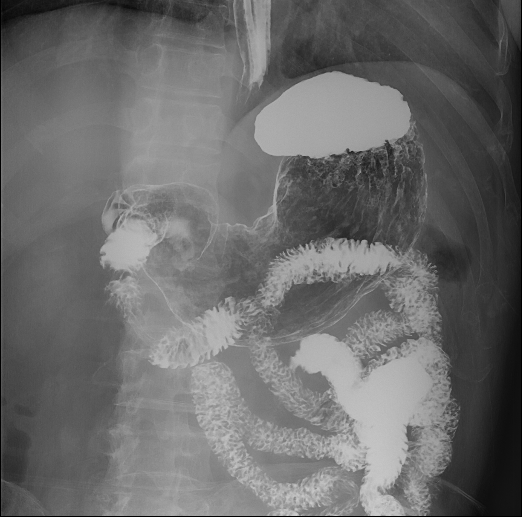

胃肠造影

肠道气钡双重造影